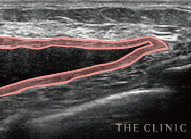

乳腺用エコーでしこりを診断

アクアフィリング豊胸やアクアリフト豊胸後の乳房内の状態を、触診だけで正確に把握することは困難です。アクアフィリング豊胸後にしこり化している場合は、位置や数、状態などを調べる必要がありますが、しこりの自覚がない方からのご相談も少なくありません。

その点、THE CLINIC では全院にデジタル乳腺用エコー「エラストグラフィ」を導入。施術前に必ずエコー検査を行い、細かい情報を把握した後、適切な治療方針を決定します。

しこりを目視しながら丁寧に除去

アクアフィリング豊胸やアクアリフト豊胸のしこりは、触診だけの曖昧な見当で取り除けるものではありません。海外では「暗闇での手術」と危険視される行為です。

THE CLINIC ではアクアフィリング豊胸やアクアリフト豊胸後のしこりを確実に溶解・除去するため、必ず乳腺用エコーを使用。最短ルートでしこりを取り除けるので、体への負担を最小限に抑えます。